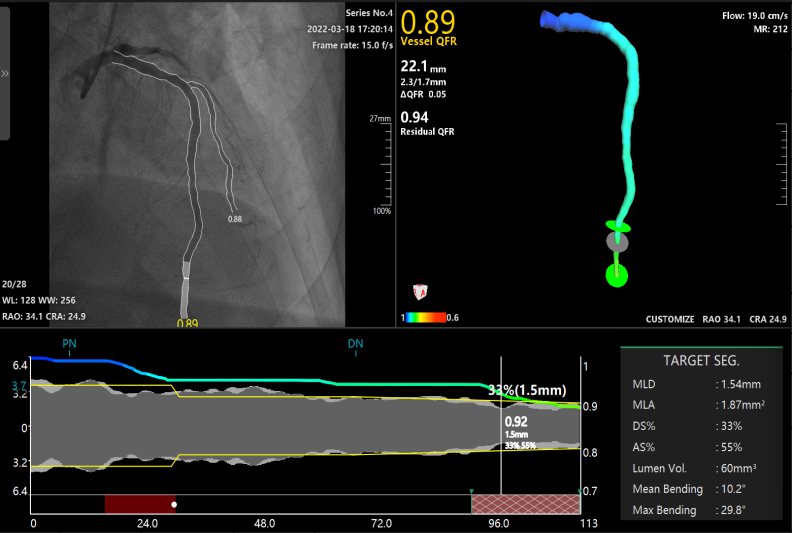

为了明确每一条血管腔的血流功能及精准指导血管支架的植入,避免植入不必要的支架,手术医生对三条血管进行了 QFR 检查,发现前降支、回旋支、右冠状动脉的 QFR 值分别为 0.89,0.21 和 0.37。根据 QFR 结果,手术医生需优先在回旋支植入支架,而对右侧血管择期治疗。

左前降支的 QFR 测定

结合 QFR 的虚拟支架技术和残余 QFR 值(Residual QFR),手术医生可以在支架植入过程中明确所需支架的大小型号及长度,并对植入后的血流恢复效果做出预判。